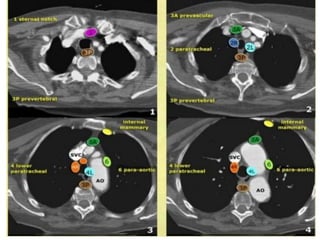

PHAÂN LOAÏI HAÏCH THEO VUØNG

American Thoracic Society

NHOÙM HAÏCH TRUNG THAÁT TREÂN (1-4)

• 1. Trung thaát cao nhaát: treân tónh maïch thaân tay ñaàu

(T).

• 2. Caïnh khí quaûn treân: treân cung ñoäng maïch chuû

nhöng döôùi tónh maïch thaân tay ñaàu (T).

• 3. Tröôùc maïch maùu hay tröôùc coät soáng.

• 4. Caïnh khí quaûn döôùi.

NHOÙM HAÏCH CHUÛ (5-6)

• 5. Döôùi ñoäng maïch chuû.

• 6. Caïnh ñoäng maïch chuû: naèm tröôùc ngoaøi ñoäng

maïch chuû leân vaø cung ñoäng maïch chuû.

NHOÙM HAÏCH TRUNG THAÁT DÖÔÙI (7-9)

• 7. Döôùi carina

• 8. Caïnh thöïc quaûn (döôùi carina).

• 9. Daây chaèng phoåi.

NHOÙM HAÏCH NAÈM ÔÛ ROÁN, GIAN THUØY,

THUØY, PHAÂN THUØY, HAÏ PHAÂN THUØY

(10-14)